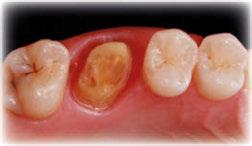

Acude a la consulta un paciente masculino de 35 años exigiendo cambios en la estética de sus dientes. El examen intraoral clínico y fotográfico reveló pérdida de estructura dentaria con facetas de desgaste en dientes anterosuperiores e inferiores, acentuándose hacia zonas oclusales de dientes posteriores.

El diagnóstico evidenció que el paciente presentaba alteración en la dinámica de la guía anterior por el desgaste de los bordes incisales, con pérdida de dimensión vertical oclusal (VDO), alteración del plano de oclusión y relaciones interoclusales inestables (Figuras 1 y 2)

dentarias, cumpliendo parámetros biológicos, terapéuticos, mecánicos y estéticos. Después se realizó un modelado digital retrospectivo (Figuras 7-11) para generar modelos impresos 3D para realizar el mock up funcional, estético y como guía para las preparaciones (Figuras 12-15). Con ello, se efectuaron las preparaciones dentarias y los registros intermaxilares y, posteriormente, se digitalizaron ambos maxilares (Figuras 16-21)

En las piezas 16 y 17 el paciente presentaba restauraciones atornilladas de metalcerámica sobre implantes oseointegrados. Se planificó realizar estas en una fase posterior a la rehabilitación de las piezas dentarias mediante flujo digital con bases de titanio y cuerpos de escaneo.